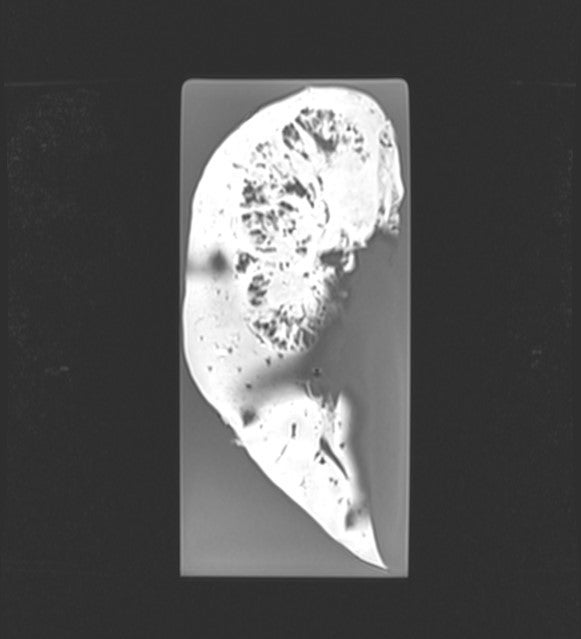

Kidney - Papillary Transitional Cell Carcinoma